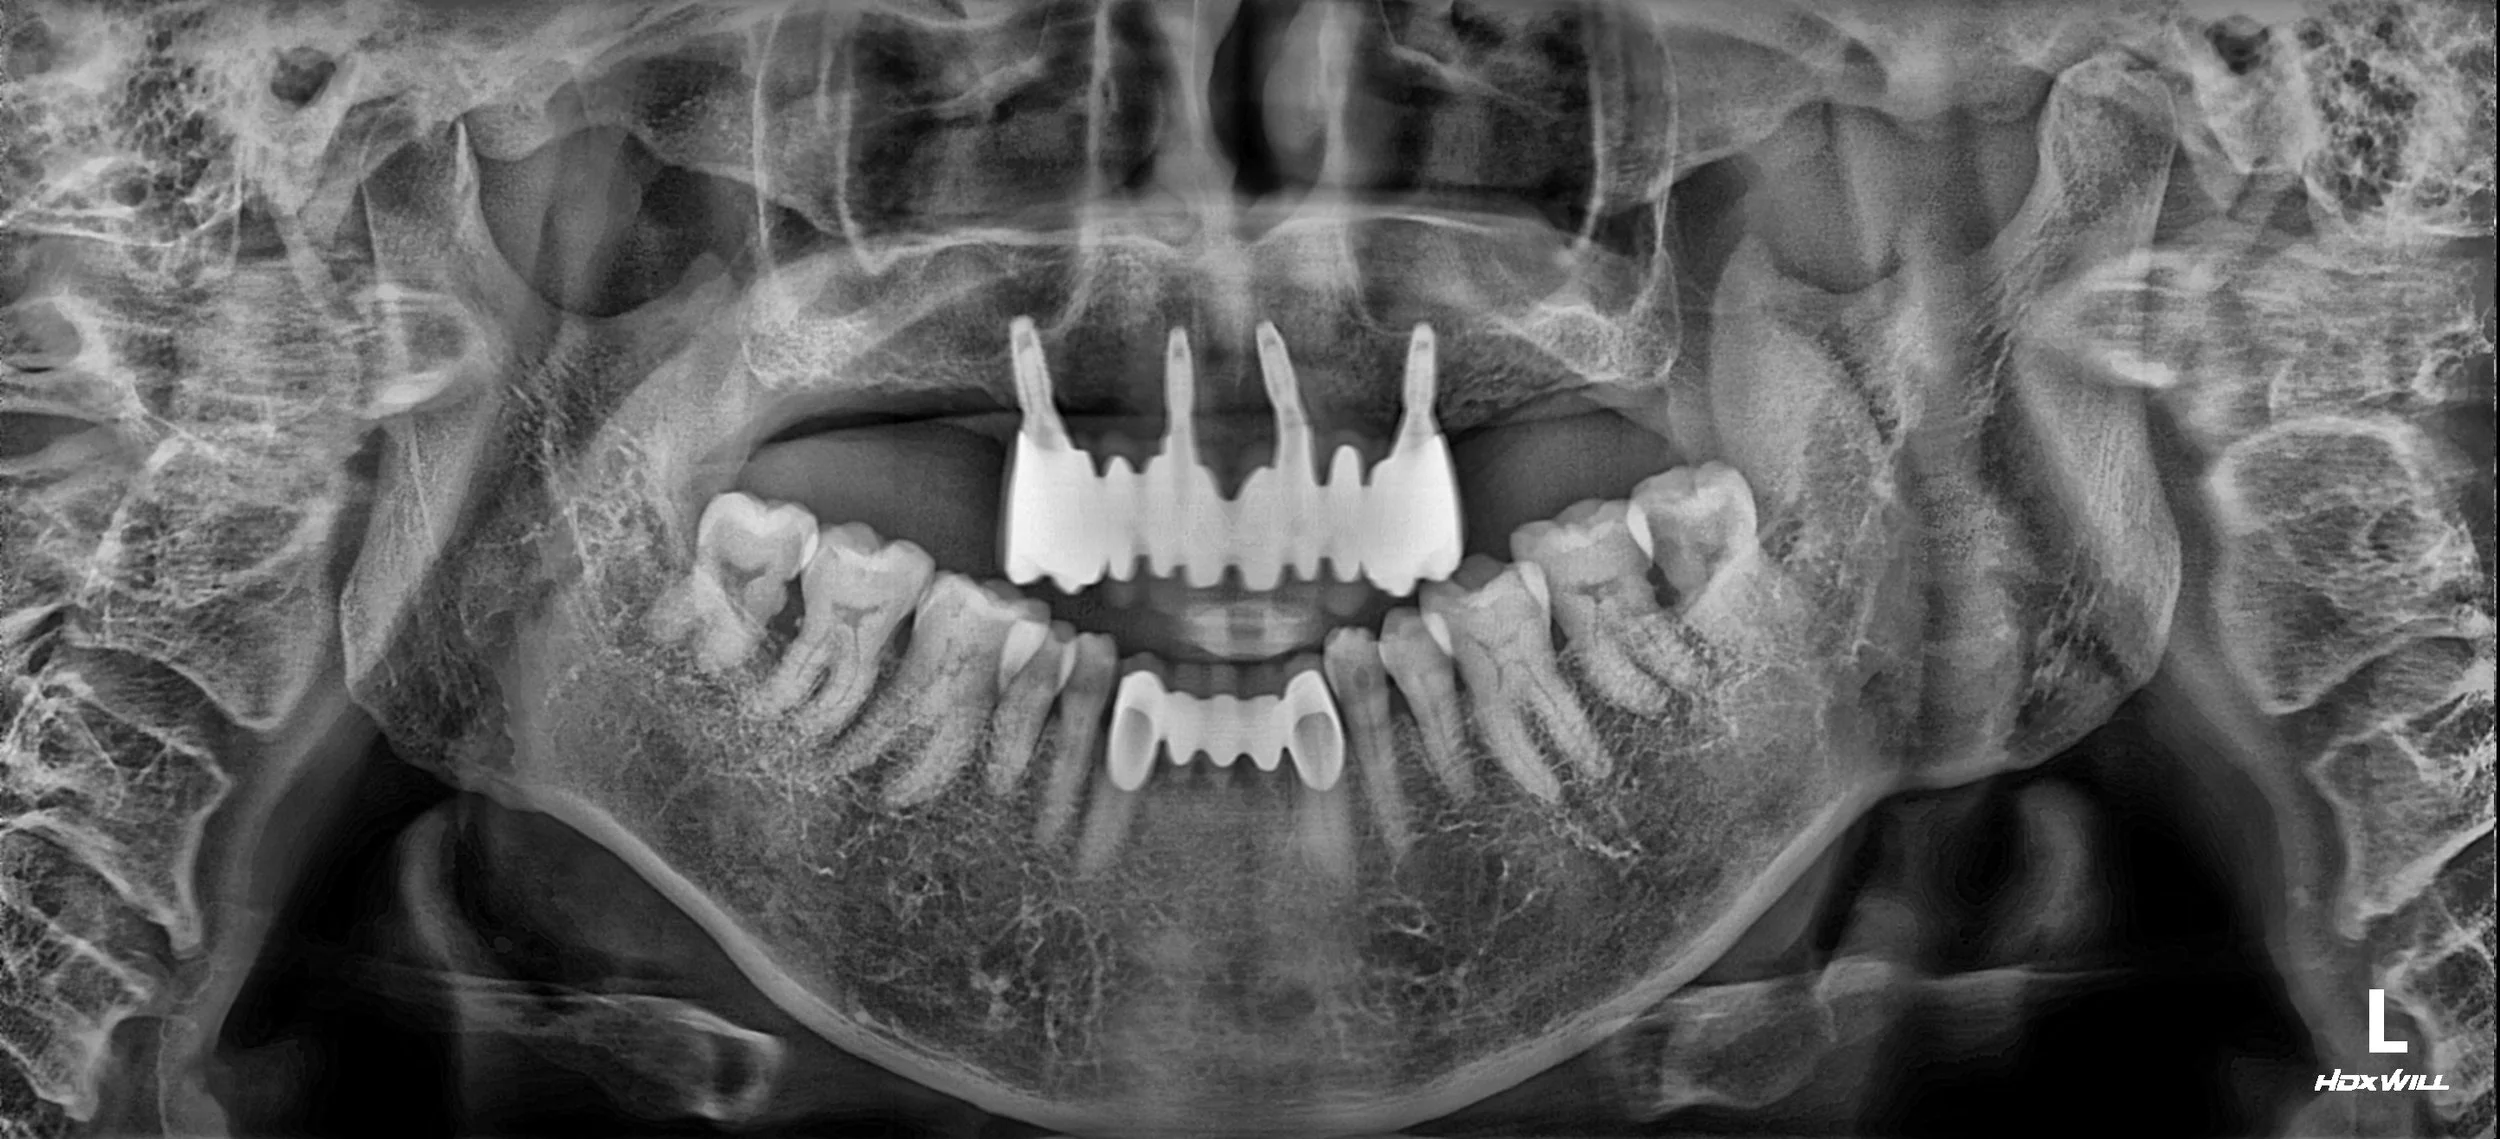

OPG - BEFORE